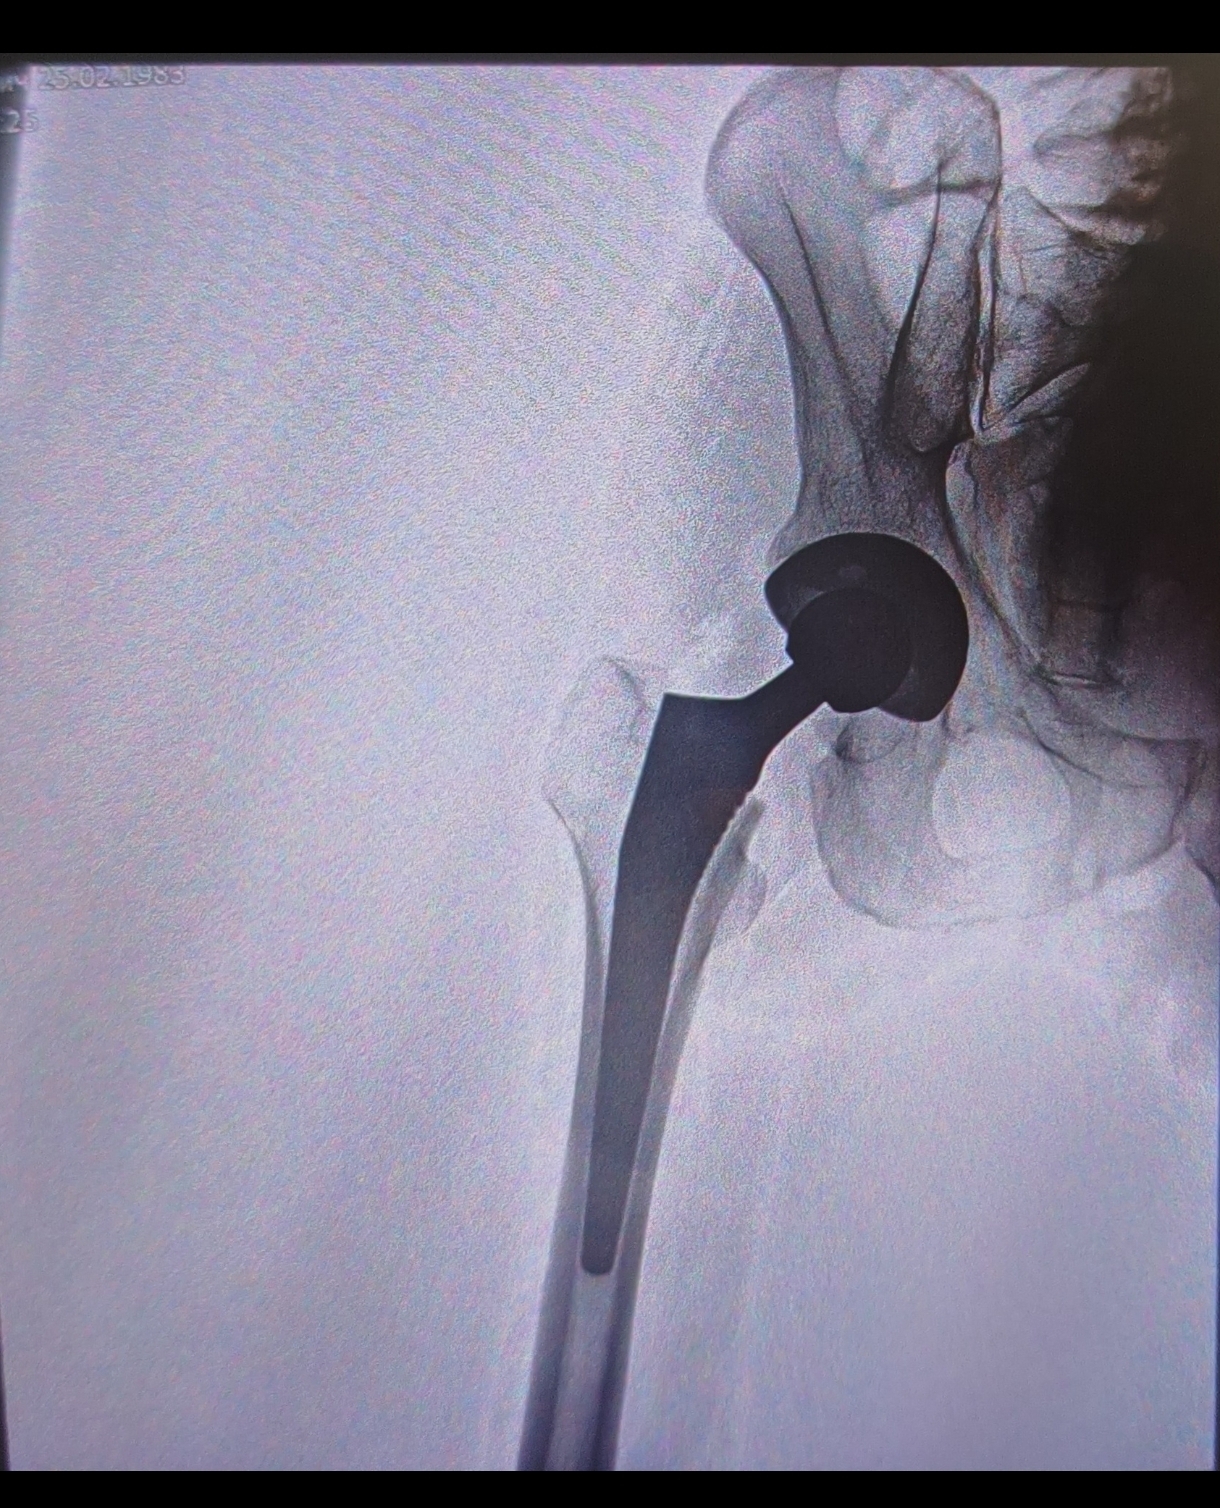

Это рентген. После него прошу показать мне его фото. Ведь у меня есть чек с указанием протеза,есть понимание и интерес посмотреть как там моя красота! И вот что я наблюдаю :

По сути своей совершенно не похожая приблуда,тем более в описании того протеза упоминались мозги которые отрабатывают движения для ускорения реабилитации. Полез искать аналог по внешним признакам и нашёл,но не смог найти производителя и цену.

Собственно о чём пост,есть ли тут люди которые разбираются в вопросе, возможно я зря паникую и всё так и должно быть,но у меня чувство,что меня банально нагрели на сотку,тот протез ушёл,а вместо него был установлен тот,что шёл по ОМС.